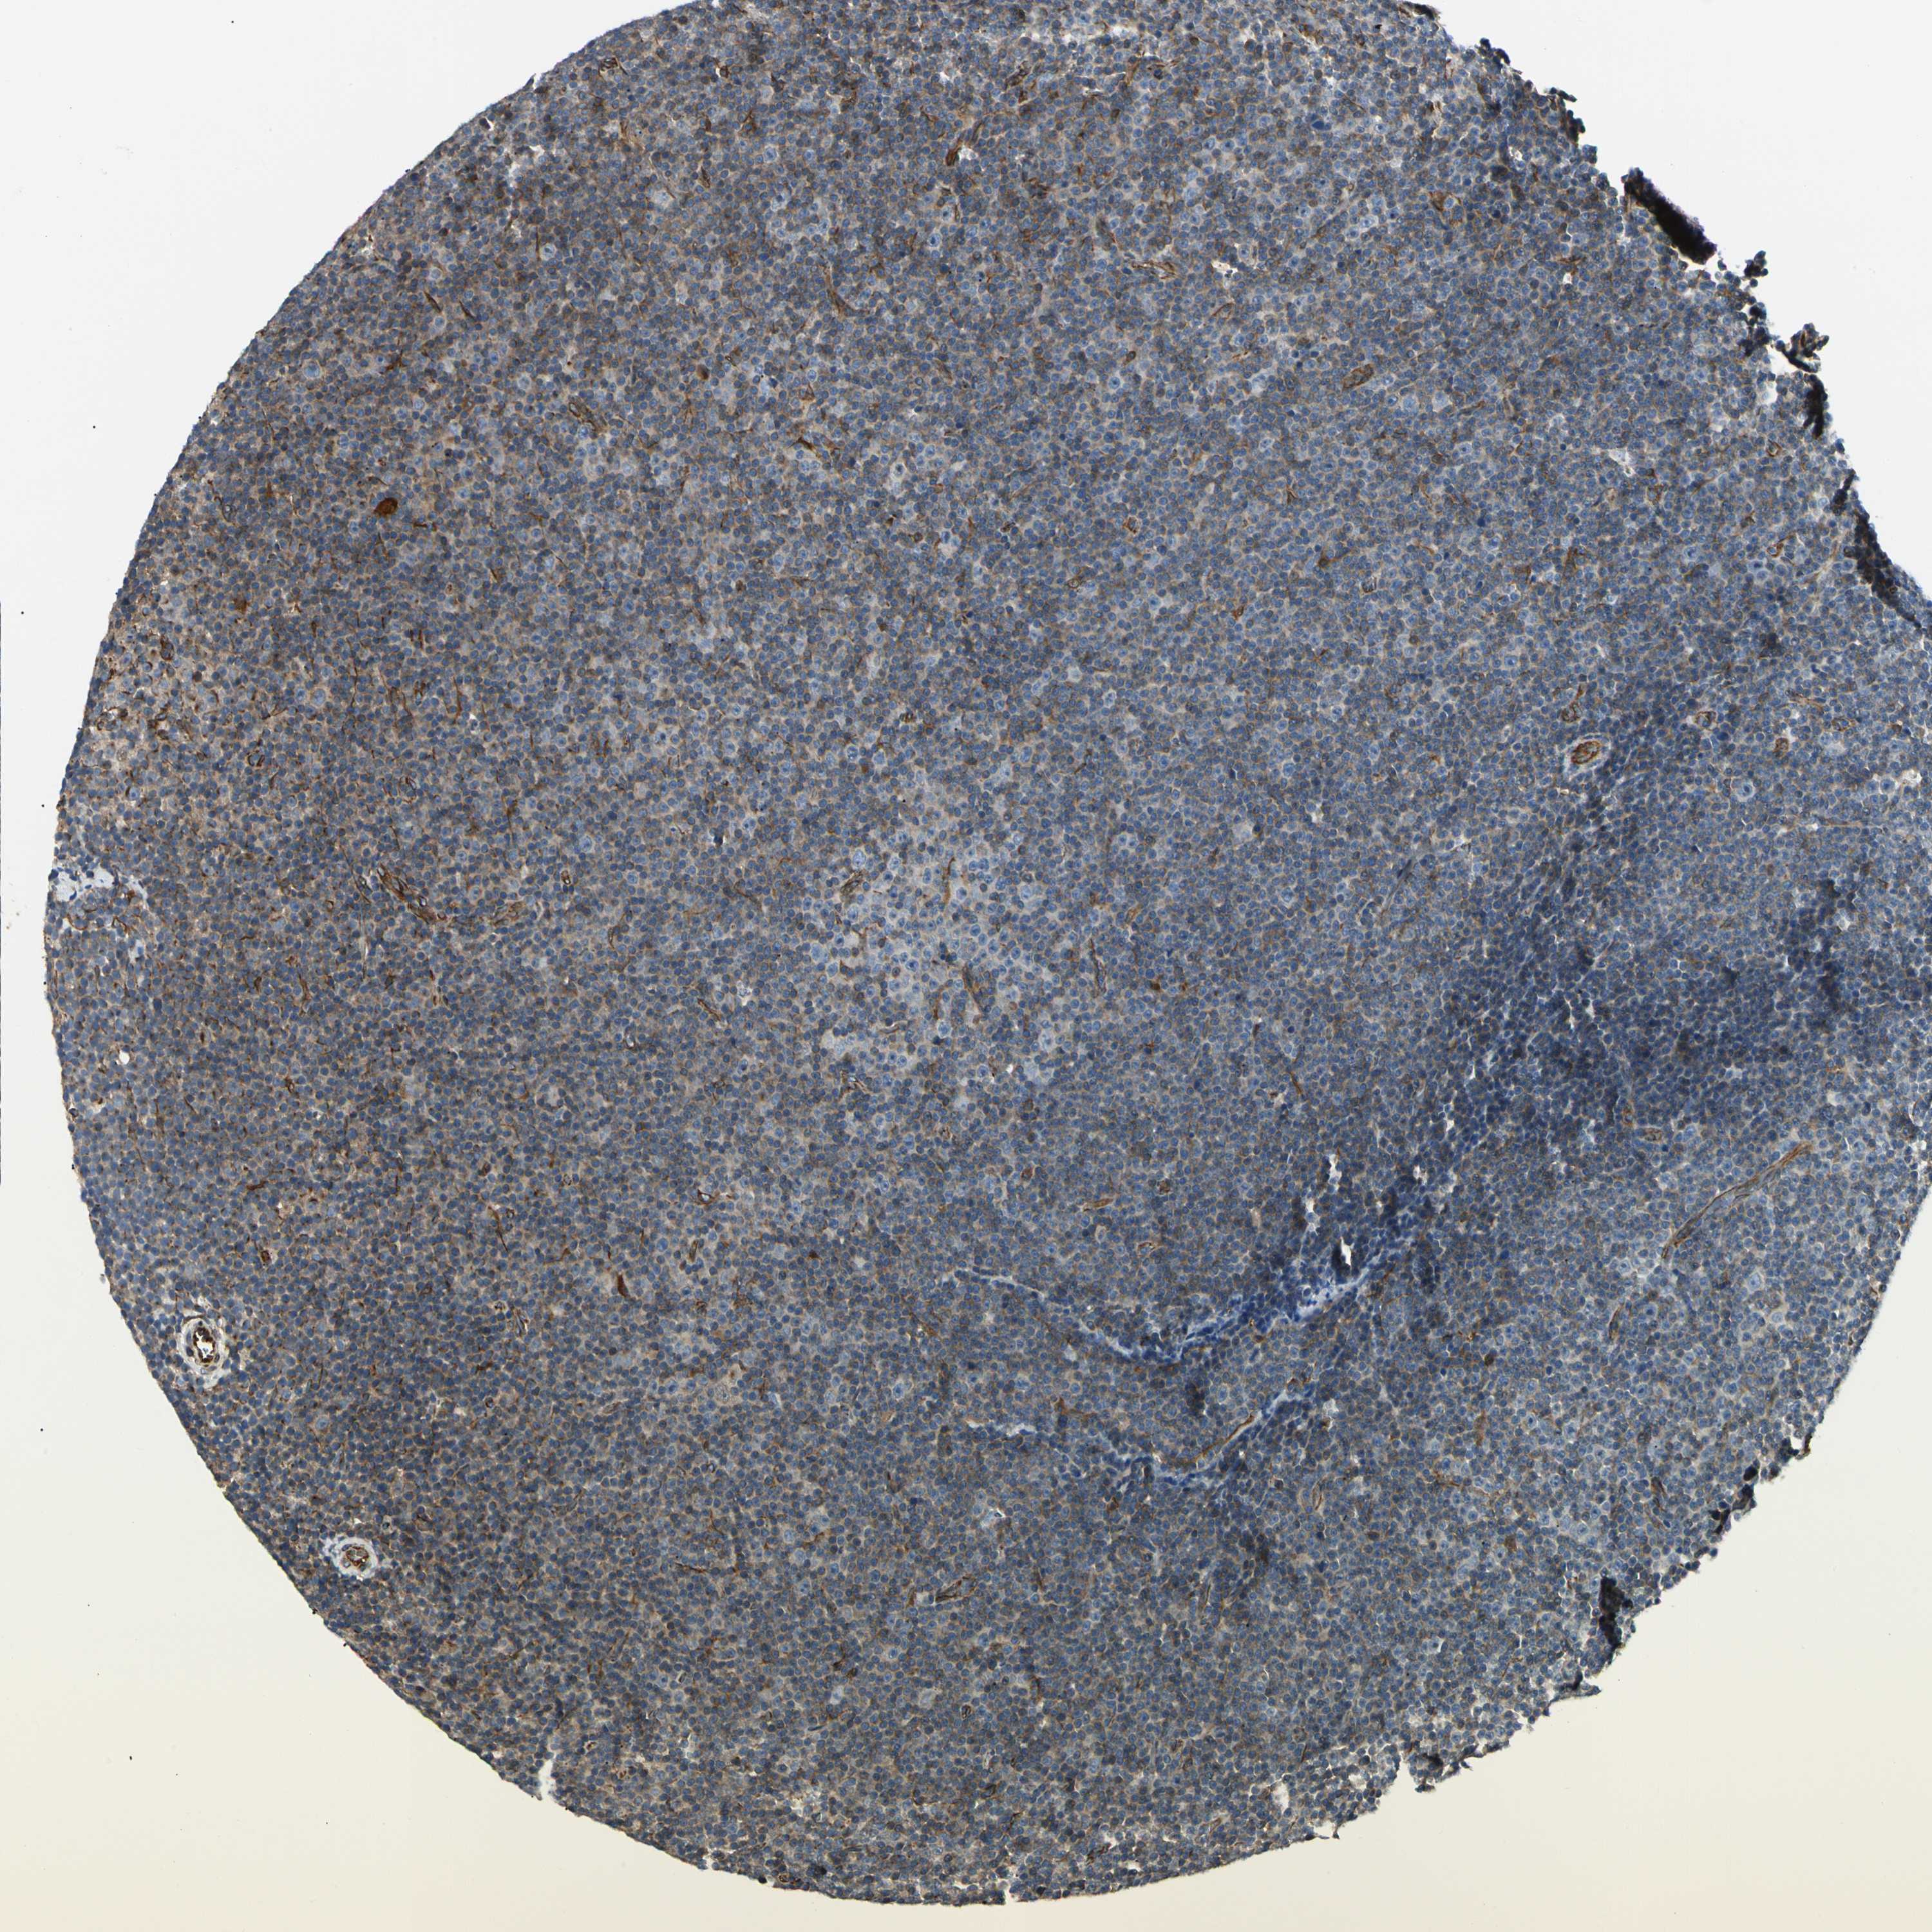

LYMPHOMA - Protein expressioni

A mouse-over function shows sample information and annotation data. Click on an image to view it in a full screen mode. Samples can be filtered based on level of antibody staining by selecting one or several of the following categories: high, medium, low and not detected. The assay and annotation is described here.

Note that samples used for immunohistochemistry by the Human Protein Atlas do not correspond to samples in the TCGA dataset.

Antibody stainingi

Antibody staining in the annotated cell types in the current human tissue is reported as not detected, low, medium, or high, based on conventional immunohistochemistry profiling in selected tissues. This score is based on the combination of the staining intensity and fraction of stained cells.

Each image is clickable and will lead to virtual microscopy that enables deeper exploration of all samples and also displays staining intensity scores, fraction scores and subcellular localization as well as patient and tissue information for each sample.

Antibody CAB008623

Staining

High

Medium

Low

Not detected

Intensity

Strong

Moderate

Weak

Negative

Quantity

>75%

75%-25%

<25%

None

Location

Nuclear

Cytoplasmic/membranous

Cytoplasmic/membranous,nuclear

Hodgkin's disease, NOS

Malignant lymphoma, non-Hodgkin's type, Low grade

Malignant lymphoma, non-Hodgkin's type, High grade